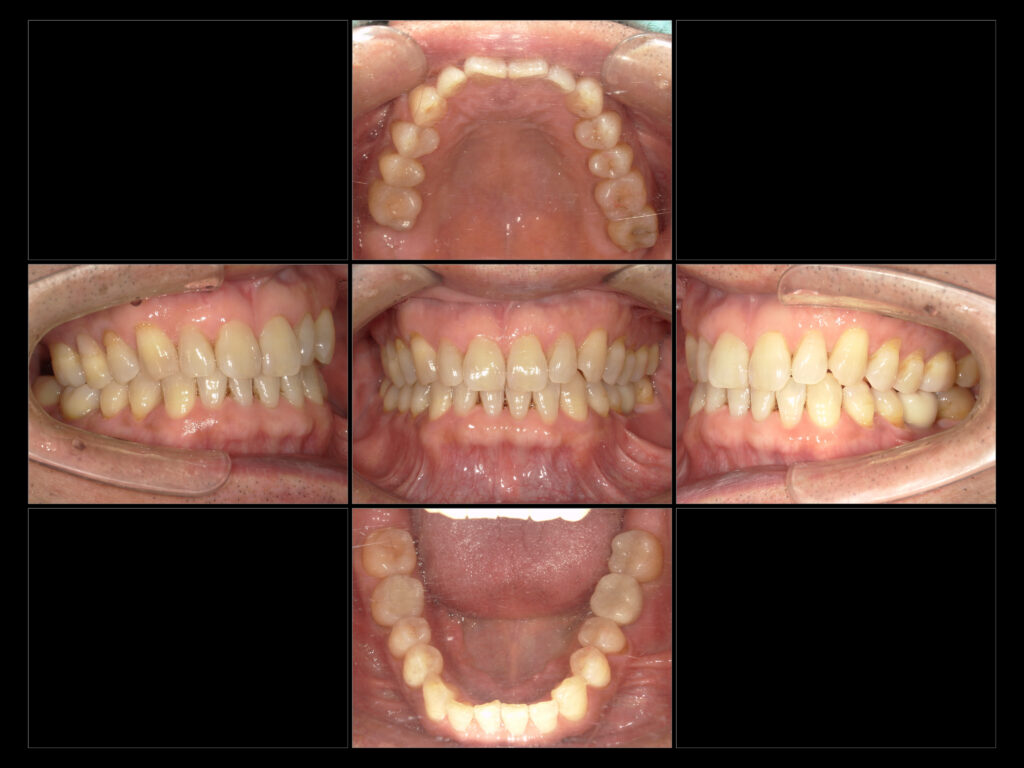

↑治療終了時口腔内写真

自然な見た目と機能性の両立を目指し、セラミック・インプラント治療を行いました!